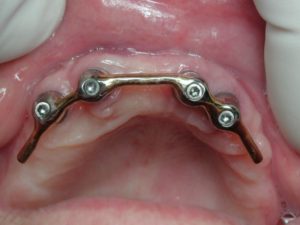

- Barre de Dolder à la mandibule

Dans cette situation, une barre de type Dolder compense plus efficacement ce porte à faux, le profil ovoïde de cette barre s’opposant plus efficacement à la bascule antérieure :